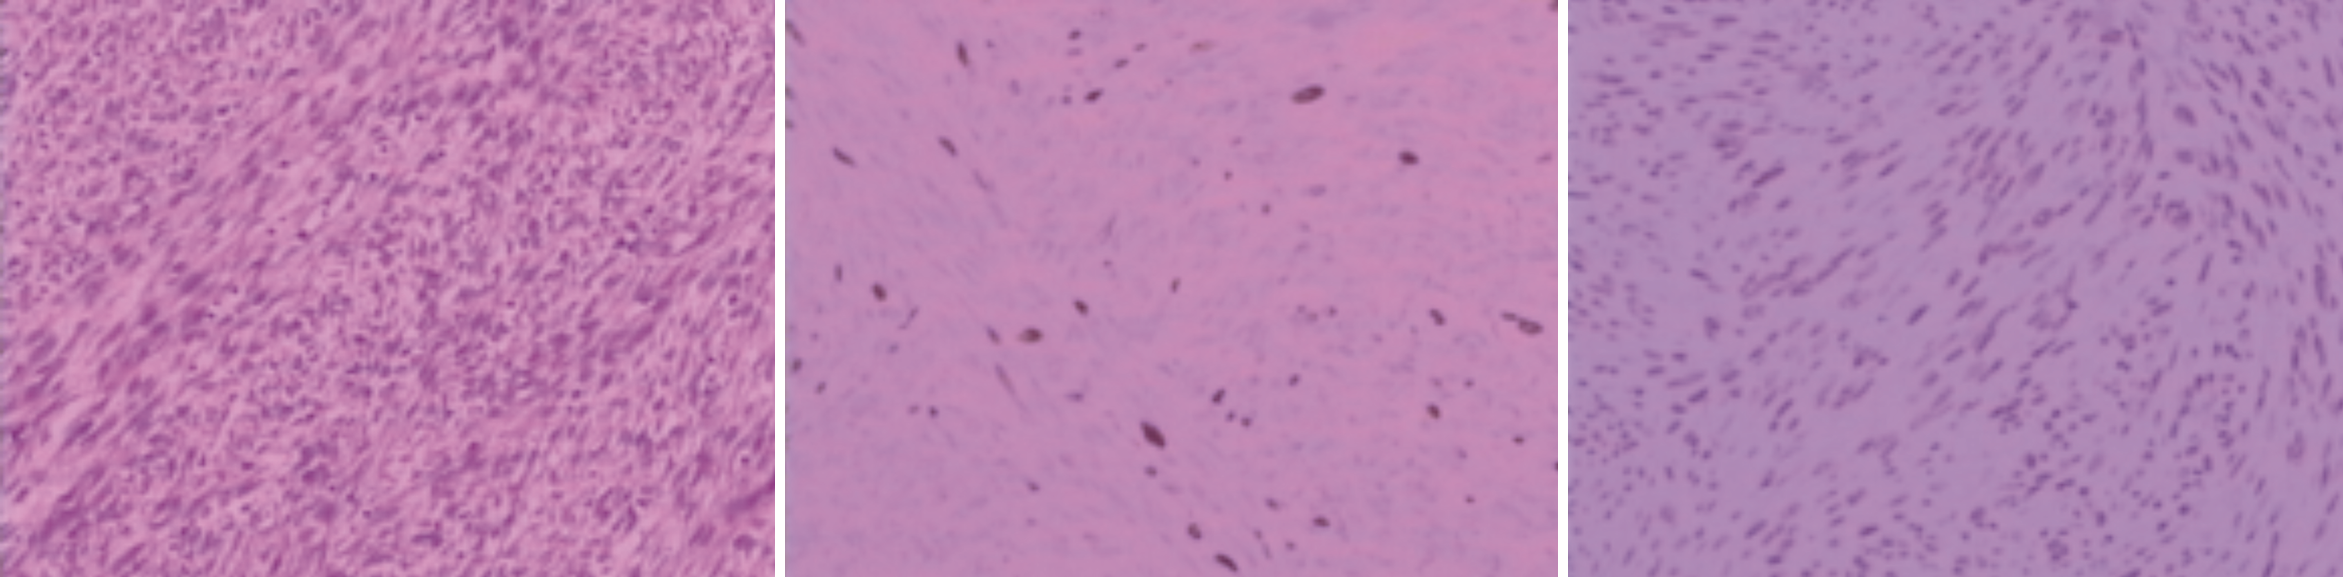

患者平素体健,既往有子宫肌瘤病史,术前胸部CT发现两肺内多发结节,未找到其他可疑的原发恶性肿瘤灶,肺内病灶初步诊断为肺转移瘤,子宫平滑肌肉瘤伴肺内转移不能排除,还需与以下表现为肺内多发结节的疾病相鉴别:(1)原发于肺的平滑肌瘤性错构瘤(pulmonary fibroleiomyomatous hamartomas,PLH):两者CT表现相似,雌、孕激素受体的表达情况可以鉴别[3]。(2)肺淋巴管平滑肌瘤病(pulmonary lymphangioleiomyomatosis,PLAM):主要表现为大小不等的囊腔及肺弥漫性间质纤维化。因肺内恶性转移不能除外,请胸外科会诊建议胸腔镜下肺结节活检术,为保证能取到足够多的标本量,采取胸腔镜下左肺上叶舌段楔形切除术,术后常规病理及免疫组化示瘤细胞ER(中等表达+90%),PR(强表达+95%),P53(+),Ki67(+约5%),SMA(+),HMB-45(-),TTF-1(肺泡上皮+),S-100(-),Desmin(+),CK(-),考虑子宫平滑肌瘤扩散(图2)。

BML为罕见病,对该病缺乏诊治指南,依据子宫肌瘤的诊治中国国家共识[4],绝经后未行激素治疗但短期内肌瘤仍生长的患者应手术治疗。同时,这类患者高分化的子宫平滑肌肉瘤不能除外,参照子宫肉瘤诊断与治疗指南(2021年版)[5]遂采取腹腔镜下全子宫两侧附件切除术。术后病理示:(全子宫)多发性平滑肌瘤,部分富于细胞,ER(+,>80%),PR(+,>90%),P53(-),Ki67(+,热点约15%),SMA(+),CD10(-),见图3。